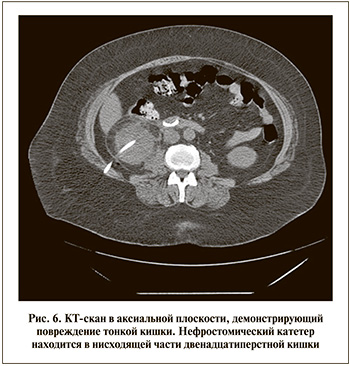

С учетом интраперитонеального расположения тонкой кишки она, как правило, находится на безопасном расстоянии от почки и риск ее повреждения во время ПНЛ чрезвычайно низок. Повреждение тонкой кишки обычно возникает при правосторонней ПНЛ на этапе пункции или дилатации пункционного хода [27]. Чаще всего повреждаются нисходящая и горизонтальная части двенадцатиперстной кишки, поскольку они ближе всего расположены к нижнему сегменту правой почки (рис. 6) [24]. Обычно перфорация возникает из-за чрезмерного продвижения иглы или инструмента и малой подвижности двенадцатиперстной кишки. Пиелография в конце операции обычно позволяет выявлять любое повреждение тонкой кишки. Появление жидкости янтарного цвета в отделяемом из нефростомического дренажа может быть следствием повреждения тонкой кишки, для дифференциальной диагностики которого необходимо проверить в ней уровень билирубина и креатинина.